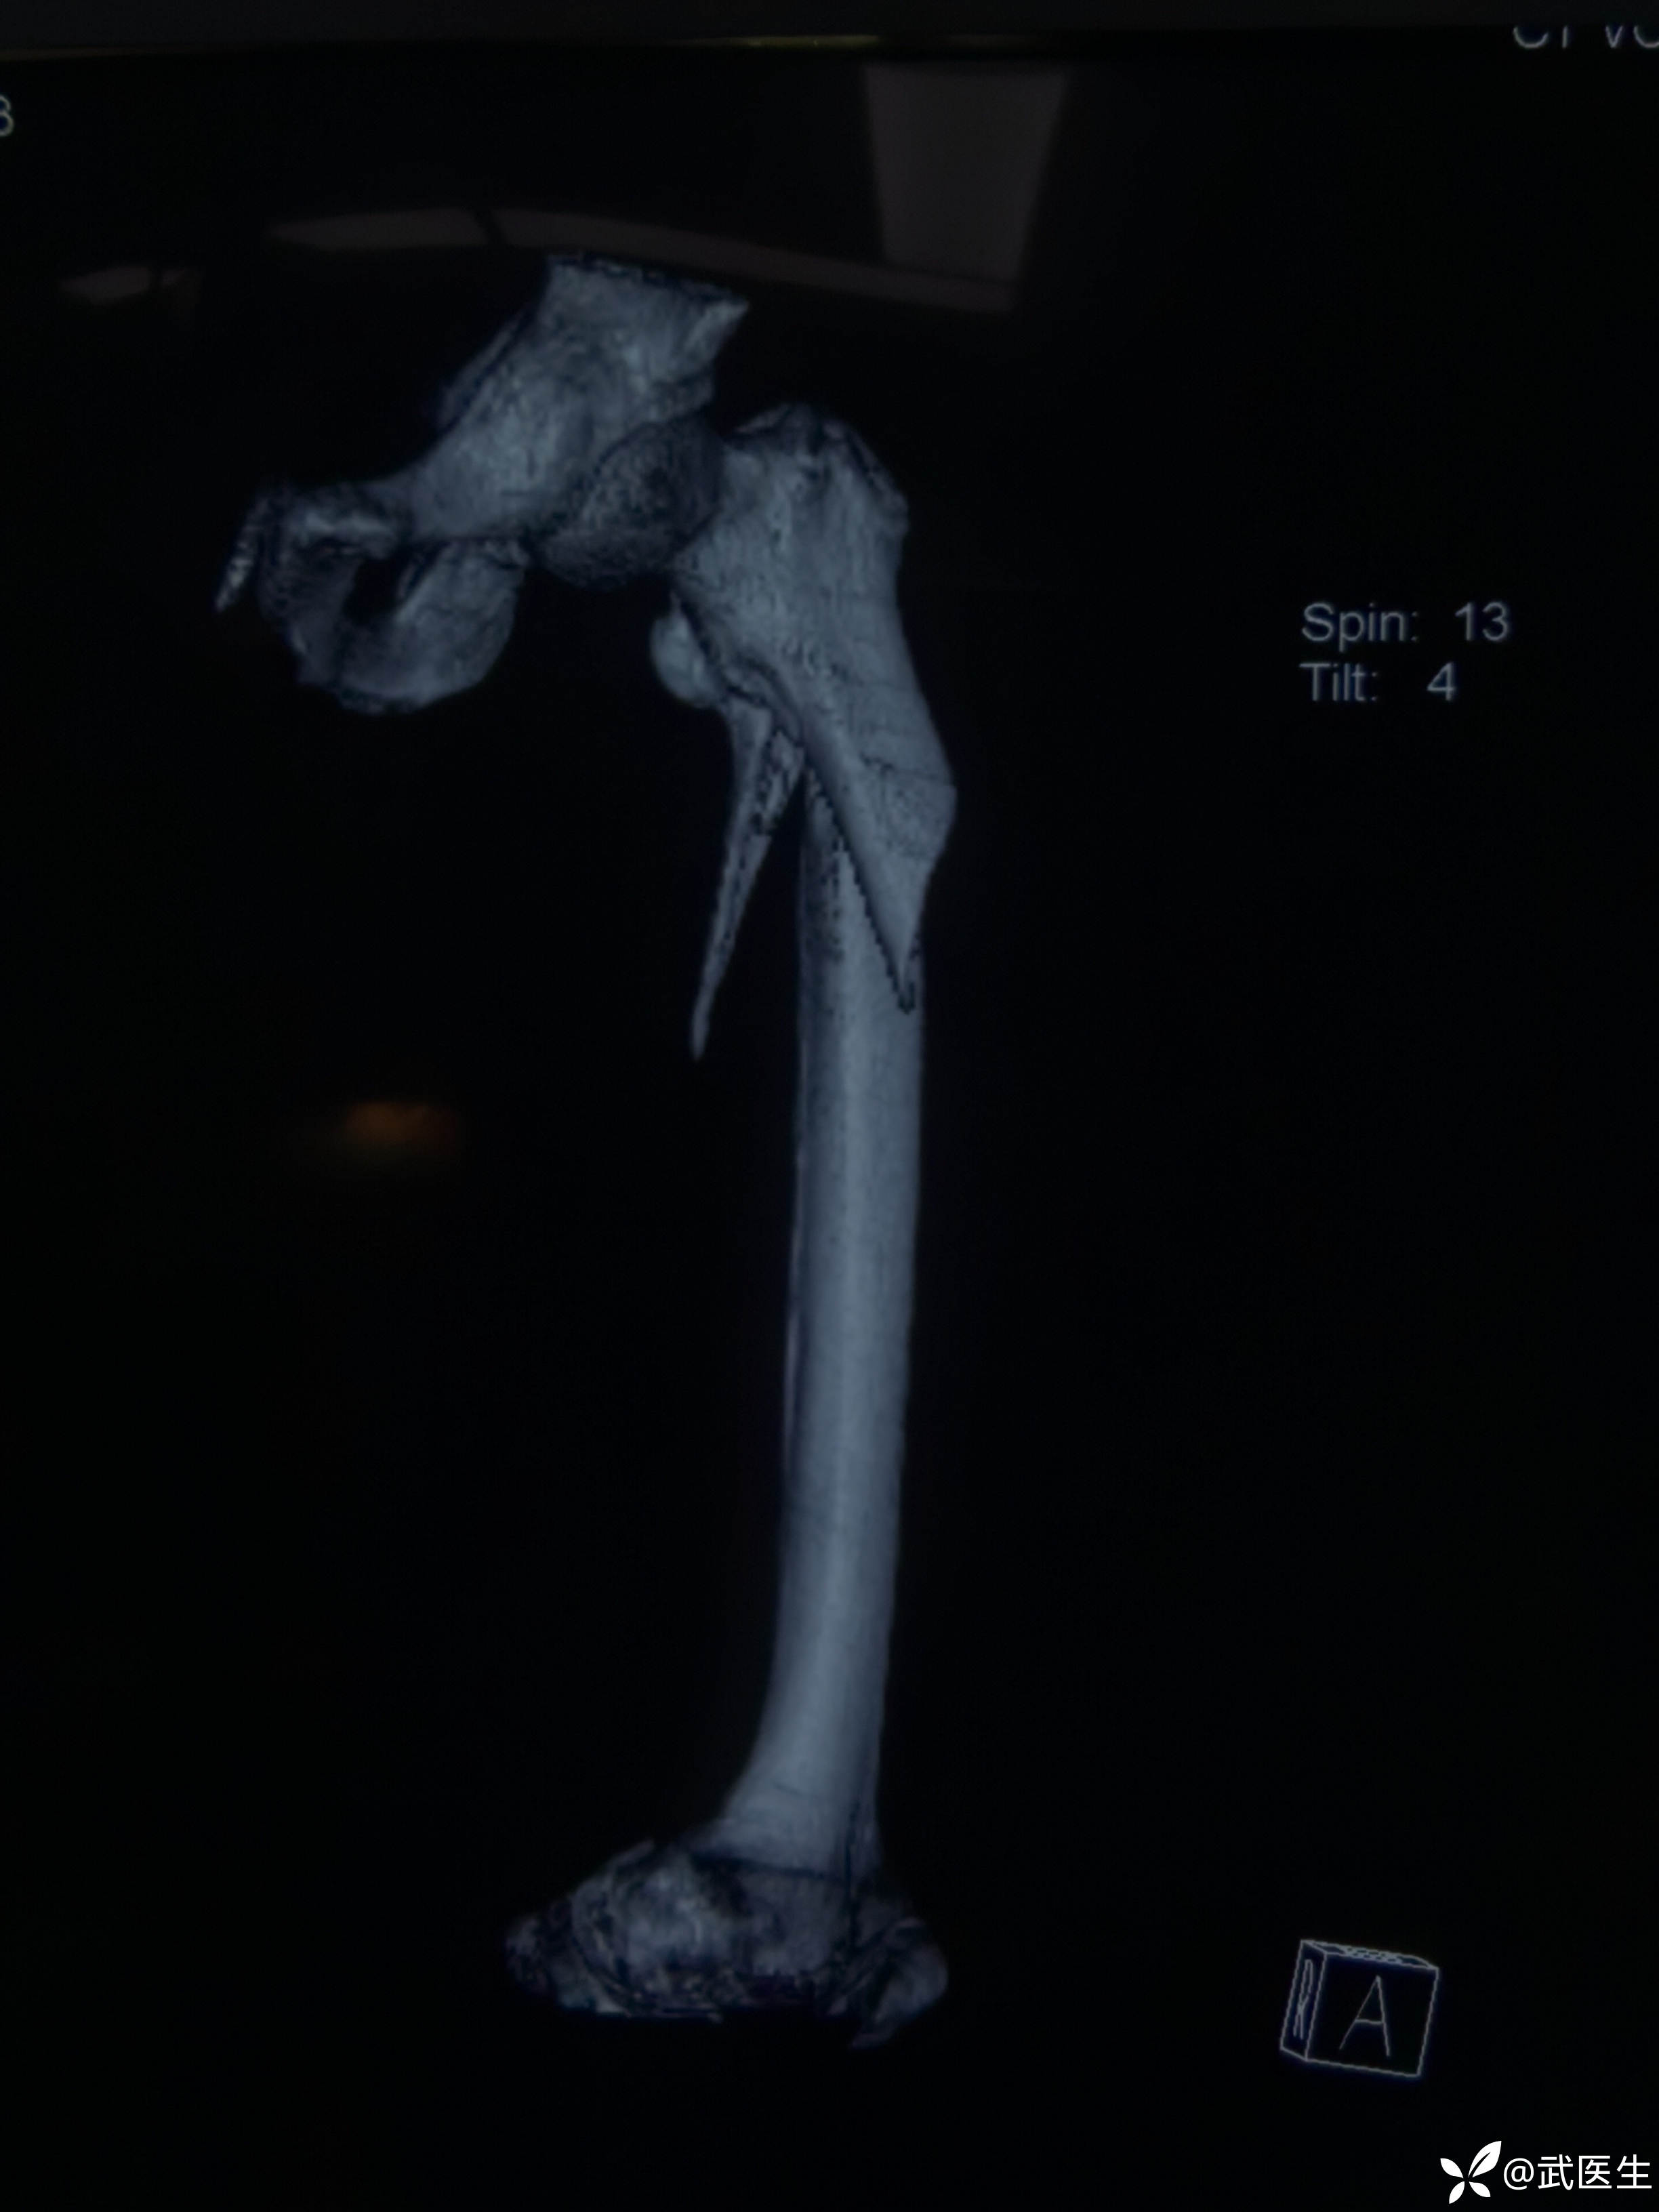

男,70岁,自己摔伤致左大腿疼痛活动受限一小时为主诉就诊,门诊以“左侧股骨近端骨折”为诊断于11月17日收住入院。上图

入院后完善检查,排除股骨转子及股骨颈骨折,无手术禁忌症,家属强烈要求手术,安排,科室讨论,使用加长PFNA,于今日18日下午(入院后第一天)安排手术。